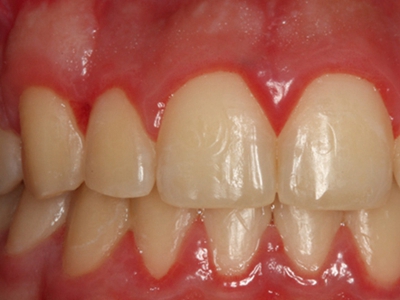

牙龈炎是发生于牙龈组织的炎症,患者可出现牙龈出血伴肿胀、发红、正常形态改变和偶尔不适等症状。本病主要由口腔卫生状况差导致,包括口腔不洁、牙菌斑等,诊断依据临床检查,治疗包括专业牙齿清洁和加强家庭口腔卫生。

牙龈炎可先引起牙齿与牙龈之间的沟(龈沟)加深,然后牙龈充血,炎症围绕一个或多个牙齿,伴牙龈乳头肿胀和易出血。一般无痛,可自行消退,也可维持轻度炎症数年。